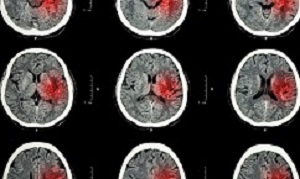

People who worked long hours had a higher risk of stroke, especially if they worked those hours for 10 years or more, according to research. Researchers reviewed data from CONSTANCES (Cohorte des Consultants des Centres d'Examens de Santé), a French population-based study group started in 2012, for information on age (18-69), sex, smoking and work hours derived from questionnaires from 143,592 participants. Cardiovascular risk factors and previous stroke occurrences were noted from separate medical interviews.

Researchers found: overall 1,224 of the participants, suffered strokes; 29% or 42,542, reported working long hours; 10% or 14,481, reported working long hours for 10 years or more; and participants working long hours had a 29% greater risk of stroke, and those working long hours for 10 years or more had a 45% greater risk of stroke.

Results: Among the 143 592 participants in the analyses, there were 1224 (0.9%) strokes, 42 542 (29.6%) reported LWH, and 14 481 (10.1%) reported LWH for 10 years or more. LWH was associated with an increased risk of stroke: adjusted odds ratio of 1.29 (95% CI, 1.11–1.49). Being exposed to LWH for 10 years or more was more strongly associated with stroke, adjusted odds ratio of 1.45 (95% CI, 1.21–1.74). The association showed no differences between men and women but was stronger in white-collar workers under 50 years of age.

Conclusions: This large analysis reveals a significant association between stroke and exposure to LWH for 10 years or more. The findings are relevant for individual and global prevention.